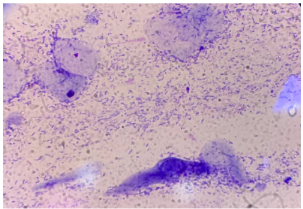

Pemeriksaan mikroskopis scraping kulit merupakan metode utama dalam konfirmasi infeksi Malassezia. Dengan teknik ini, sel jamur berbentuk bulat hingga lonjong dengan tunas monopolar yang khas dapat diidentifikasi secara langsung (Sudipa dkk, 2021). Kombinasi antara pemeriksaan Wood’s lamp dan mikroskopis meningkatkan akurasi diagnosis serta membantu dalam menentukan terapi yang lebih tepat untuk menangani infeksi Malassezia pada anjing.

Pemeriksaan Mikroskopis scraping kulit

Pemeriksaan mikroskopis scraping kulit adalah metode diagnostik yang umum digunakan untuk mendeteksi keberadaan Malassezia pada kulit anjing. Sampel diambil dengan mengerok area tepi lesi menggunakan pisau bedah steril, kemudian ditempatkan pada kaca objek dan ditetesi dengan larutan kalium hidroksida (KOH) 10% untuk melarutkan keratin. Setelah itu, sampel

diperiksa di bawah mikroskop untuk mengidentifikasi sel-sel jamur. Malassezia spp. memiliki morfologi khas berupa sel bulat hingga lonjong dengan dinding tebal dan tunas monopolar (Sudipa dkk, 2021). Dalam sebuah penelitian, pemeriksaan mikroskopis scraping kulit pada anjing dengan dermatitis menunjukkan adanya sel-sel Malassezia yang berproliferasi, mengonfirmasi peran jamur ini dalam patogenesis dermatitis pada anjing (Pribadi, 2015).